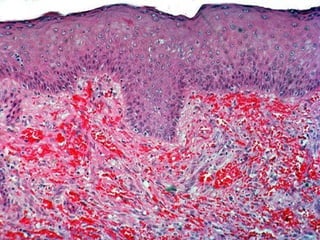

• #86 Pemphigus, fresh bullae

• #87 Pemphigus, ruptured, scabbed bullae

• #88 Acantholysis in the bullous family of diseases. Notice that the “seperation” can be within the acanthocytes, i.e., the stratum spinosum, or at the dermal-epidermal junction. So would you imagine many of the bullous disorders are diseases of basement membrane and tonofibrils (i.e., desmosomes), and may be autoimmune?